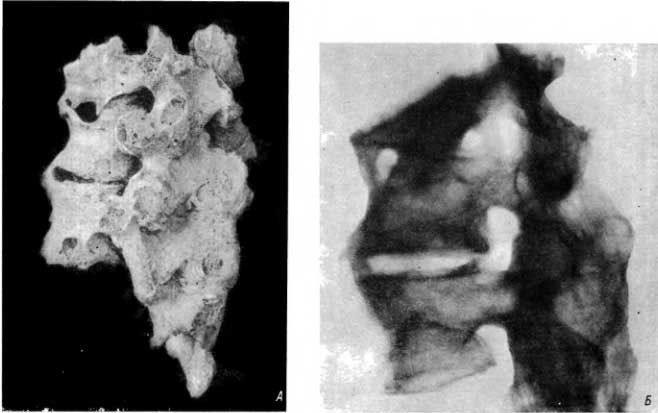

На рис. 24 — кости пожилого мужчины из погребения I в. до н. э. из кургана вблизи г. Бийска. Поясничные позвонки, крестец, обе подвздошные кости и большой вертел левой бедренной кости подверглись патологической деструкции. Тела и дуги всех поясничных позвонков слиты с крестцом и между собой в одно целое (рис. 24, А). В позвонках, соединенных между собой при помощи костного блока, видна большая полость (рис. 24, Б). В ней имеется крупный секвестр.

Рис. 24. А — туберкулезный спондилит с образованием обширного костного блока; Б — на рентгенограмме видна крупная полость с секвестром в верхнем позвонке, соединенном с нижерасположенным при помощи костного блока.

Перед нами хотя и тяжело, но несомненно весьма хронически протекавший туберкулезный спондилит, сопровождавшийся натечными абсцессами, с поражением не только большого отдела позвоночника, но и таза, и одной из бедренных костей.